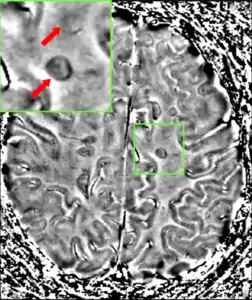

Magnetic resonance imaging (MRI) of the brain and spine may show areas of demyelination (lesions or plaques). Gadolinium can be administered intravenously as a contrast agent to highlight active plaques, and by elimination, demonstrate the existence of historical lesions not associated with symptoms at the moment of the evaluation.[70][71]

Central vein signs (CVSs) have been proposed as a good indicator of MS in comparison with other conditions causing white lesions.[72][73][74][75] One small study found fewer CVSs in older and hypertensive people.[76] Further research on CVS as a biomarker for MS is ongoing.[77]